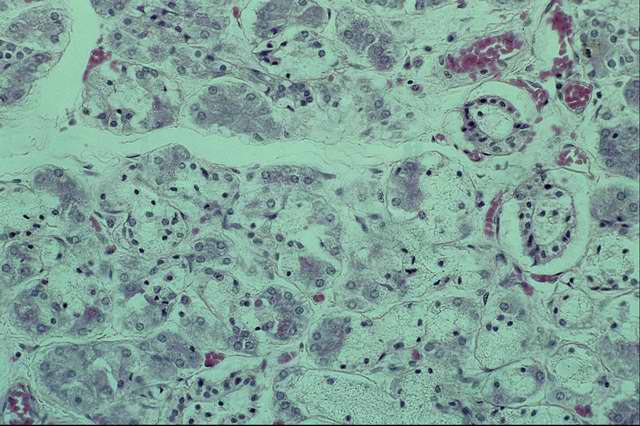

Амилоидоз печени характеризуется образованием амилоида в вокруг синусоидном пространстве (пространстве Диссе) между звездчатыми ретикулоэндотелиоцитами и печеночными клетками (рис. 8). Амилоид отмечают также в стенках междольковых капилляров и артериол. По мере накопления амилоидного вещества печень увеличивается в размере, приобретает бледно-коричневый цвет, более плотную, а у лошадей дряблую консистенцию. У лошадей она может достигать массы 16—33 кг, при этом около 10% случаев заканчиваются разрывом печени в связи с расплавлением стромы (А. П. Гиндин, 1959), появляются кровоподтеки, которые нередко заканчиваются смертельным кровоизлиянием в брюшную полость.